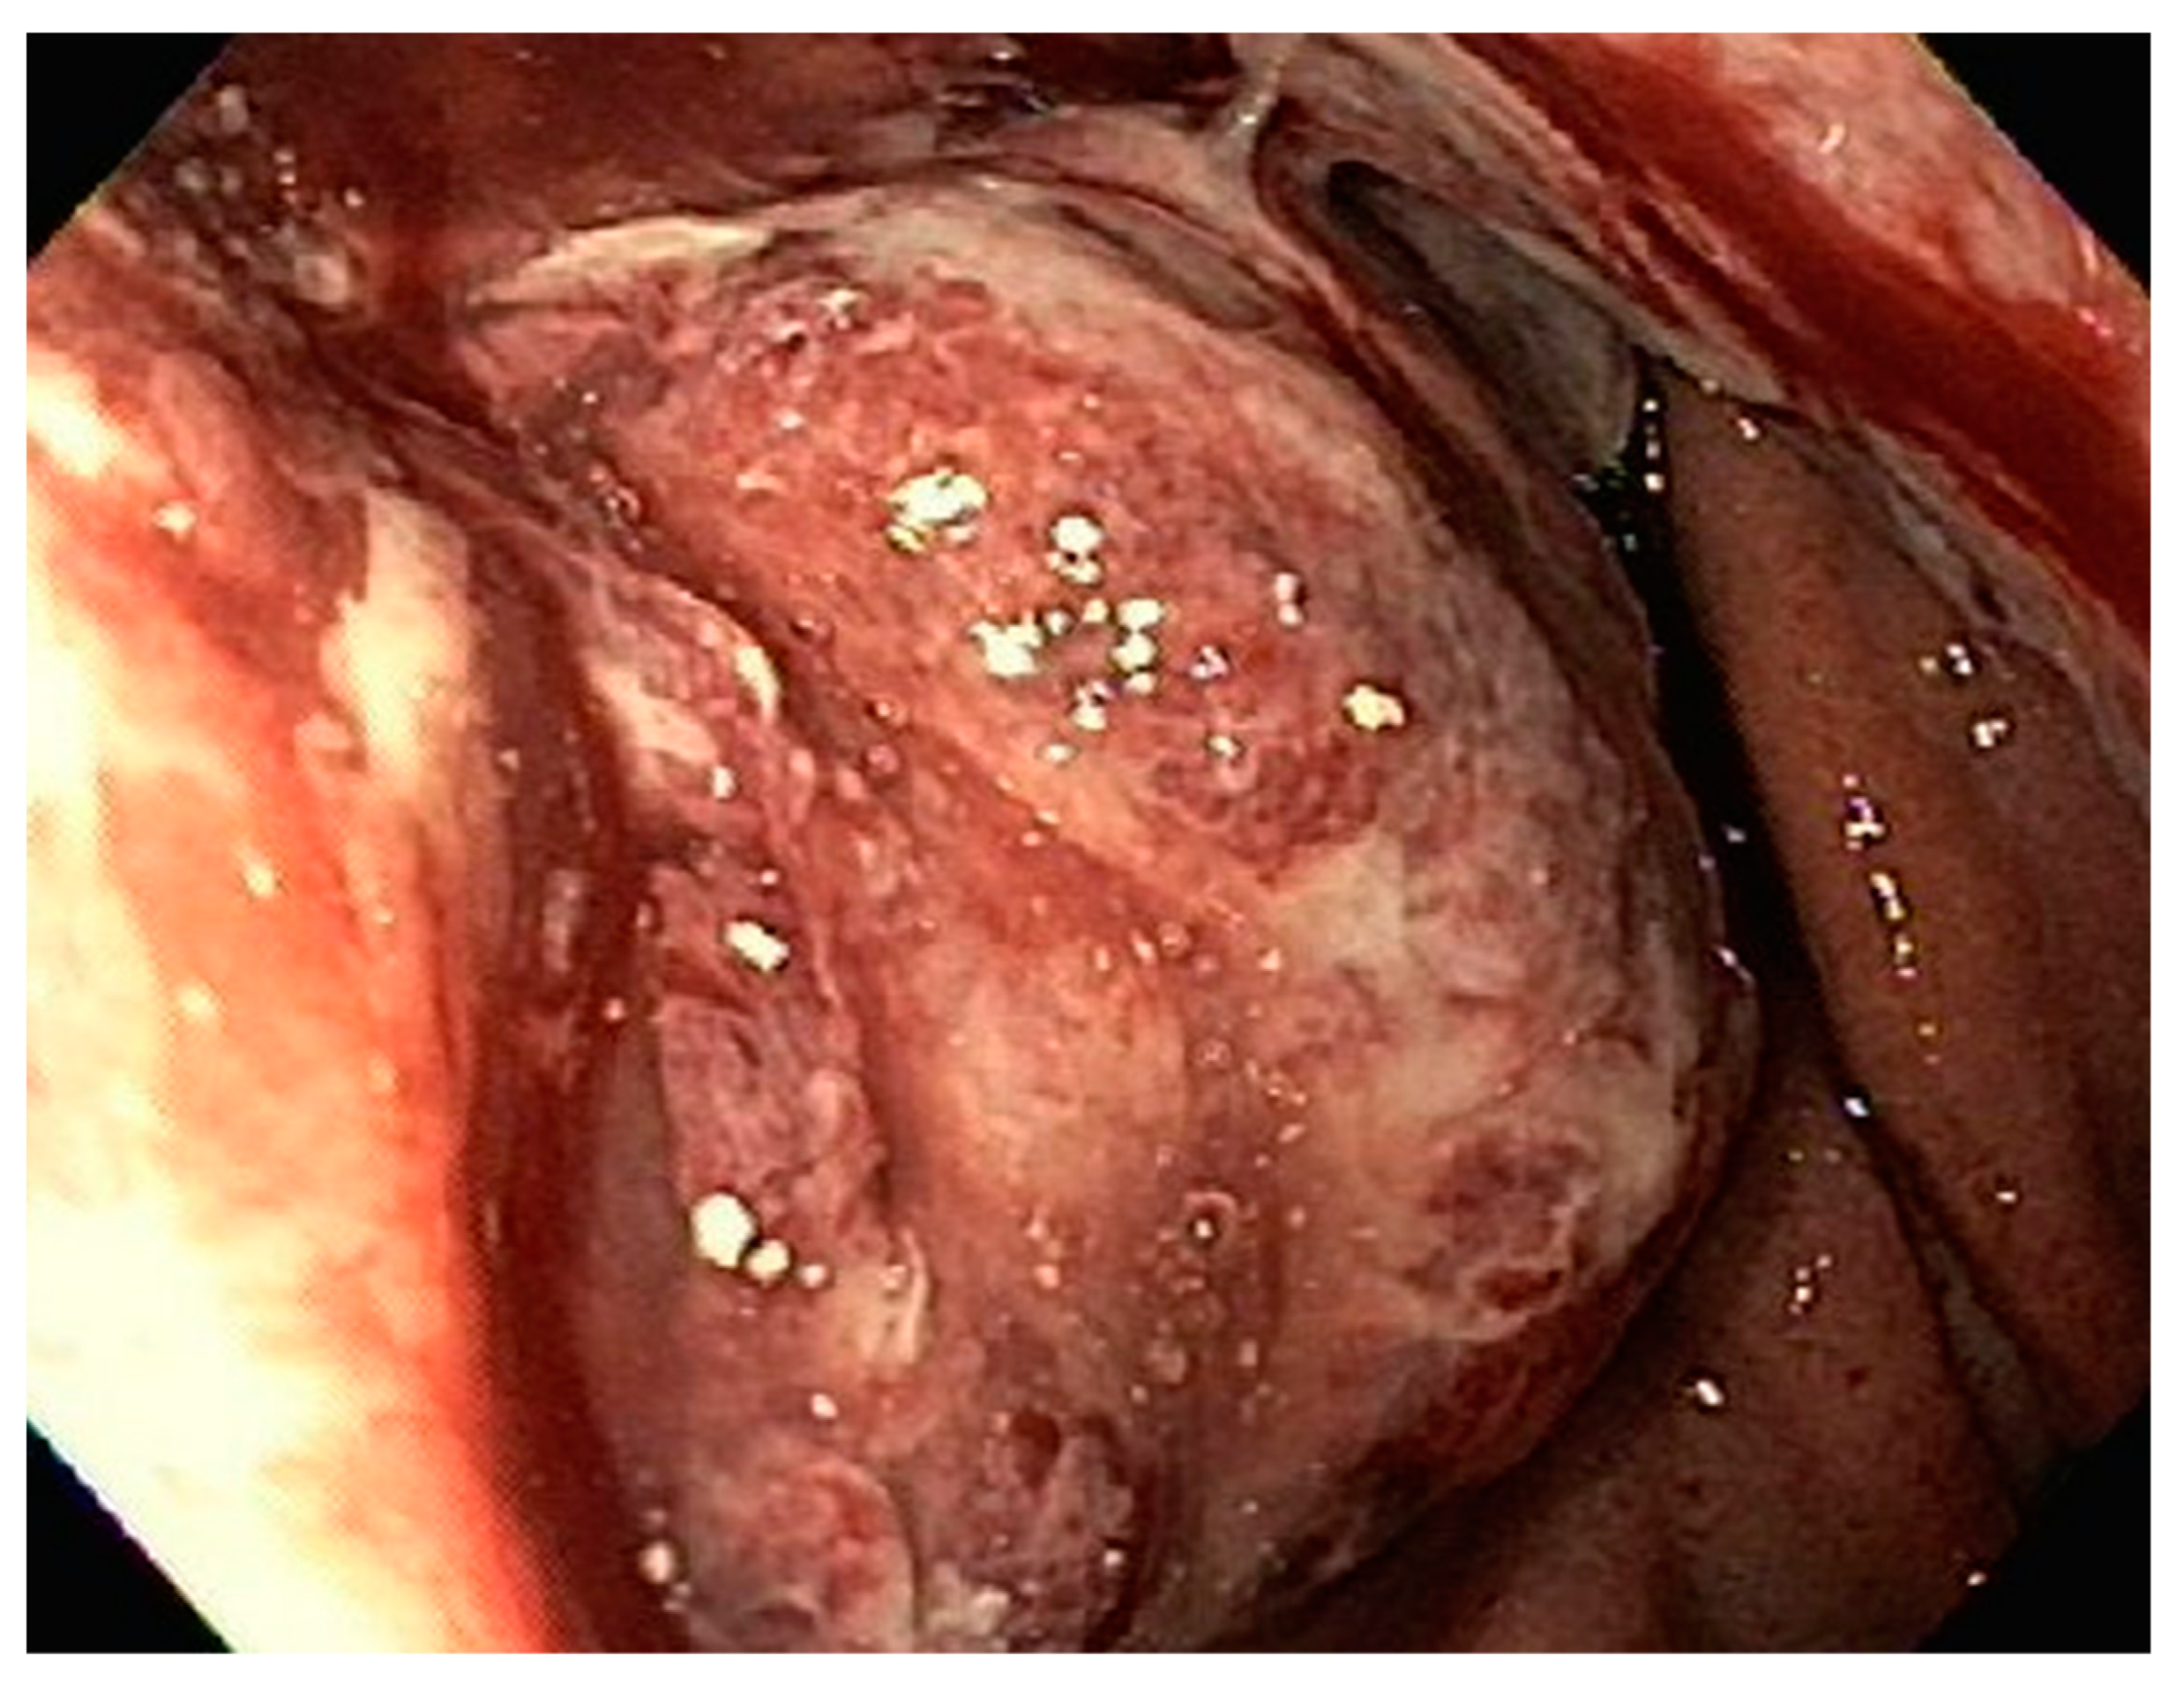

| 1 | F | 66 | Skin | Fundus, cardia, and body | Polypoid lesions with superficial ulcers | Esophagus, duodenum, mediastinum, cervical soft tissue, pancreas | Metastatic malignant melanoma | Radiotherapy and immunotherapy | Comfort care and death 5 days after EGD diagnosis of metastasis |

| 2 | M | 84 | Lymphoid | Fundus and cardia | Ulcerated and necrotic mass | Liver, urinary bladder | Diffuse large B-cell lymphoma | None | Death in 2 months after EGD diagnosis of metastasis |

| 3 | F | 35 | Lung | Fundus | Fungating mass | Esophagus, mediastinum | Large-cell neuroendocrine carcinoma | Chemotherapy-carboplatin/ etoposide | Death 1 month after EGD diagnosis of metastasis |

| 4 | F | 73 | Kidney | Fundus and body | Multiple large friable masses | Liver and lungs | Clear cell renal carcinoma | Nephrectomy, chemotherapy, immunotherapy (Axitinib) | Death 10 days after EGD diagnosis of metastasis |

| 5 | M | 76 | Lung | Body | Cratered ulcers | Liver, bone and adrenals | Small cell carcinoma (poorly differentiated neuroendocrine Ca) | None | Death 7 days after EGD diagnosis of metastasis |

| 6 | M | 61 | Lymphoid | Unknown | Clean based ulcer | None | Marginal zone lymphoma | Rituximab, Zanubrutinib, umbrasilib. OCHOP regimen currently | Progressive disease per latest scans despite therapy |